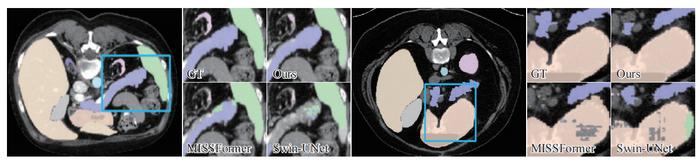

image: The segmentation details produced by different methods are shown in focus in the blue rectangular box areas. The proposed method performs better than other methods.

Connecting the MCA decoder to the MSCAN backbone yields researchers’ network, named MCANet. From the figures in this paper, it can be seen that this proposed method, with less computational complexity, achieves the best results on a series of widely-used benchmark datasets, including skin lesion segmentation, nuclei segmentation, abdominal multi-organ segmentation, and polyp segmentation. Also, it can be observed that this proposed method performs better when dealing with changes in individual size and shape, etc. In summary, researchers’ contributions can be summarized as follows: